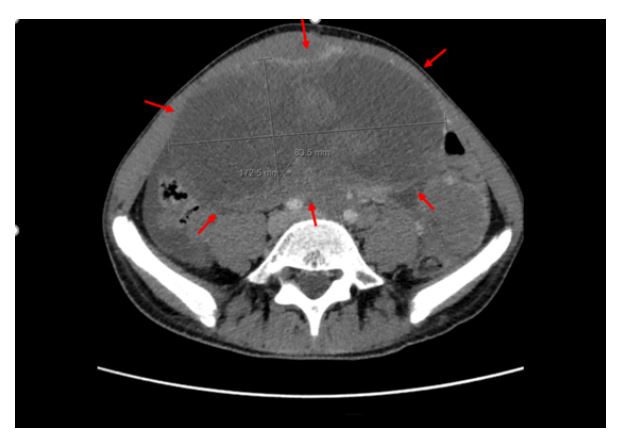

To further characterize these findings, an abdominopelvic computed tomography scan was performed (Figure 2), which revealed a midline mesenteric mass measuring 17.3 x 8.4 cm, along with multiple other ill-defined masses in the abdominal, retroperitoneal, and pelvic regions with areas of necrosis highly suggestive of an aggressive neoplastic process. In addition, there was evidence of peritoneal carcinomatosis and liver metastases. Complete blood count and biochemistry, including uric acid and lactate dehydrogenase levels, were within normal ranges.